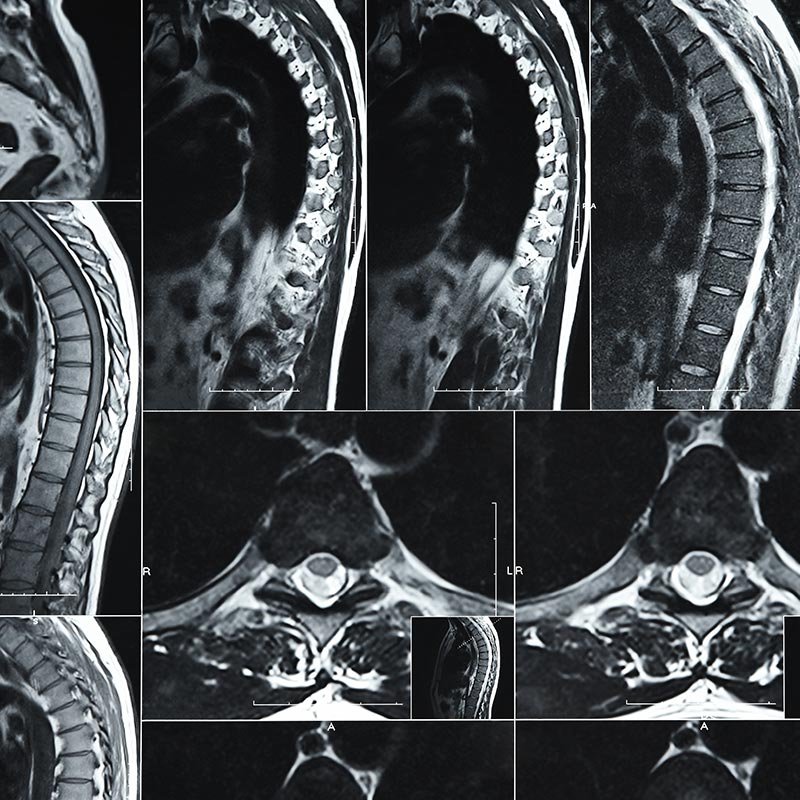

Conteúdos atualizados sobre coluna vertebral, com orientações médicas, prevenção, tratamentos para dor na coluna e informações seguras para cuidar melhor da sua saúde.